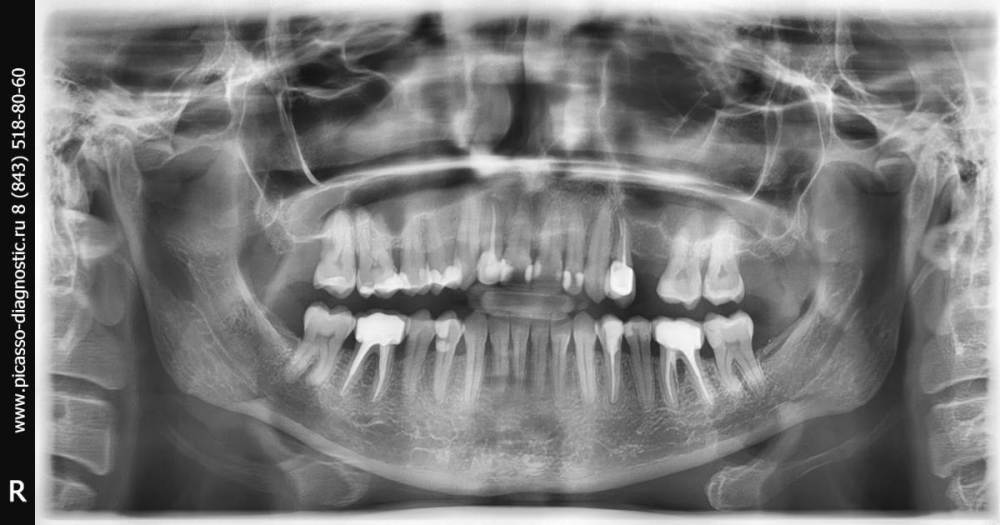

Ulitka Опубликовано 31 марта, 2021 Поделиться Опубликовано 31 марта, 2021 Добрый вечер. Около месяца назад стоматолог лечил мне 26, 27 и 35 зубы. Через пару дней появились болезненные ощущения при пережевывании пищи, реакция на холодное/горячее и просто иногда болезненные ощущения появлялись, даже без всякого воздействия на зубы. К стоматологу попала только через 10 дней . Подшлифовали пломбы, немного получше стало, но полностью болезненные ощущения не прошли. Скоро снова пойду к своему стоматологу. А что Вы можете сказать по снимку? Воспаление, может, где-то? И какие еще проблемы есть, исходя из снимка? Ссылка на комментарий

red_butler Опубликовано 1 апреля, 2021 Поделиться Опубликовано 1 апреля, 2021 11 часов назад, Ulitka сказал: Воспаление, может, где-то? 3.6 зуб, нужен прицельный снимок, похоже воспаление между корней 11 часов назад, Ulitka сказал: И какие еще проблемы есть, исходя из снимка? пародонтит Ссылка на комментарий